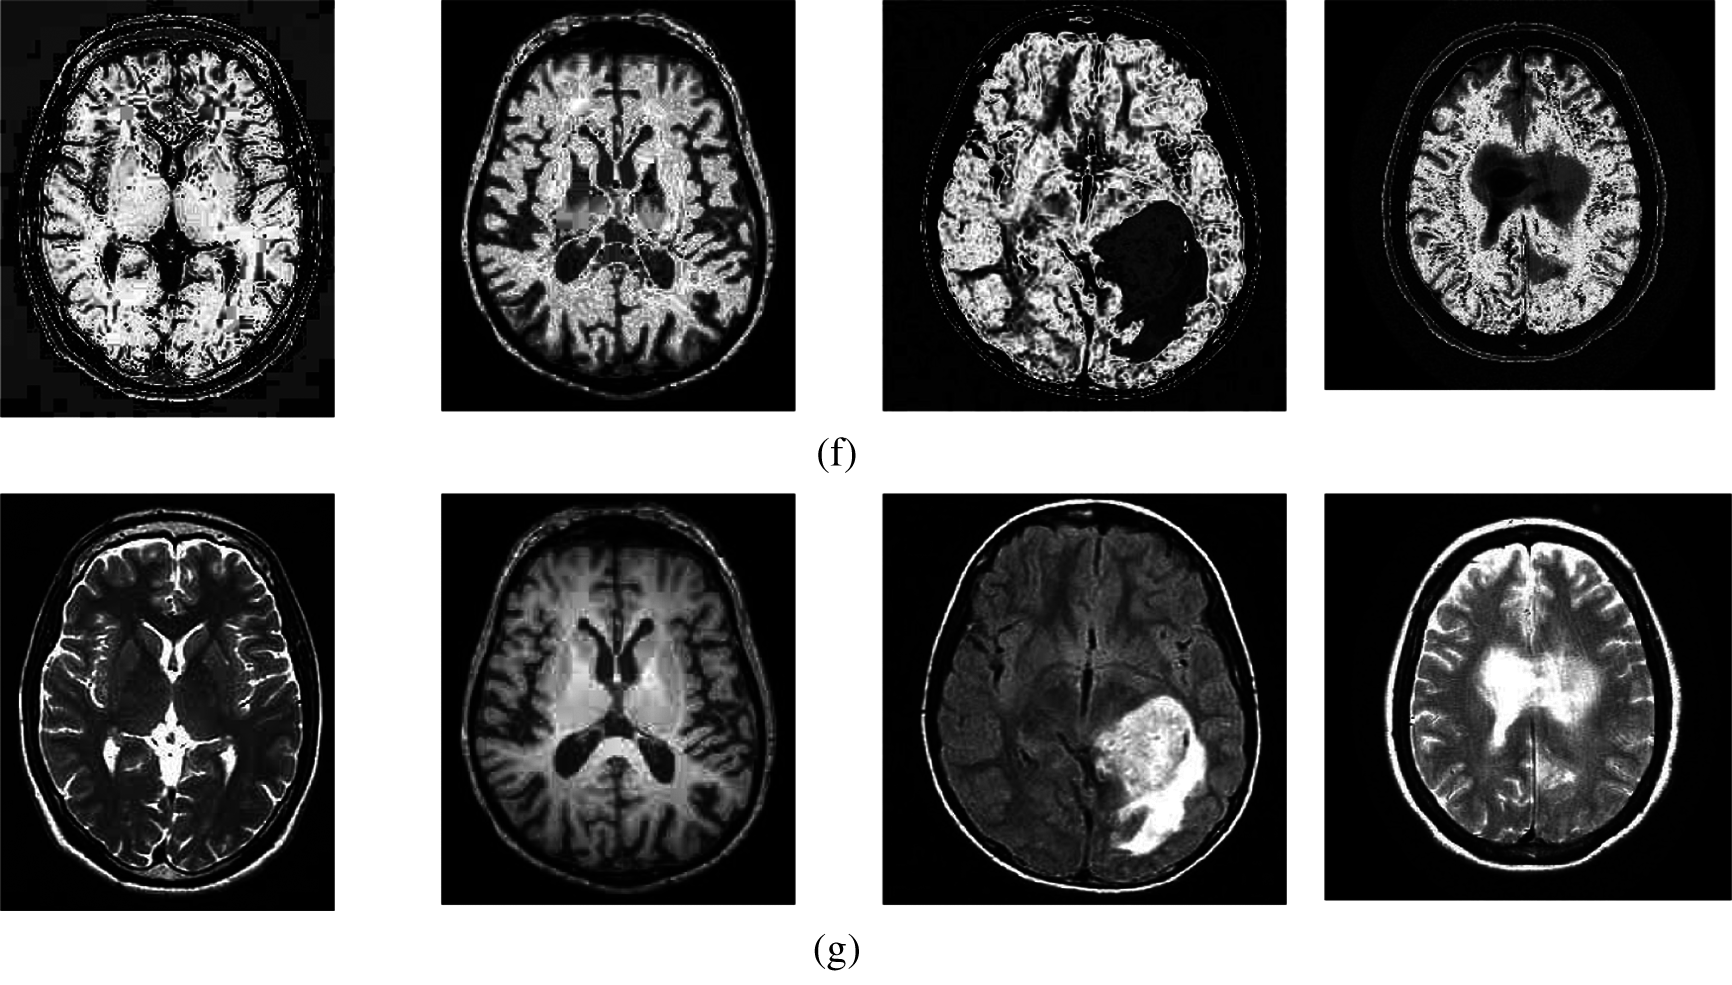

The qualitative results of the proposed and the existing methods are illustrated in Fig. 3. It can be seen that all of the images have different trends with the dark and bright areas. When we compare the enhancement results of existing methods with the suggested method, the proposed method shows better enhancement results than the existing methods in terms of image quality. In the case of the existing method, it could be seen that FPDEs methods [25] (Fig. 3f) produce over-enhanced images, while the proposed method yields natural appearance by enhancing the dark areas and maintaining the bright areas of input images.

Figure 3: The brain MRI enhancement results of the proposed and existing enhancement models. (a) Input image, (b) Al-Shamasneh et al., (c) Raghunandan et al., (d) Z. Al-Ameen, (e) X. Fu et al., (f) FPDEs, (g) Proposed method

Overall, the brightening caused by the proposed model makes the structures of the medical images, which usually represent boundaries, well defined and clear. This is accredited to the model's capability to capture high frequency details efficiently. The proposed method introduces fair visual results for the weakly illuminated images. This is the contribution of the fractional integral entropy in this study.